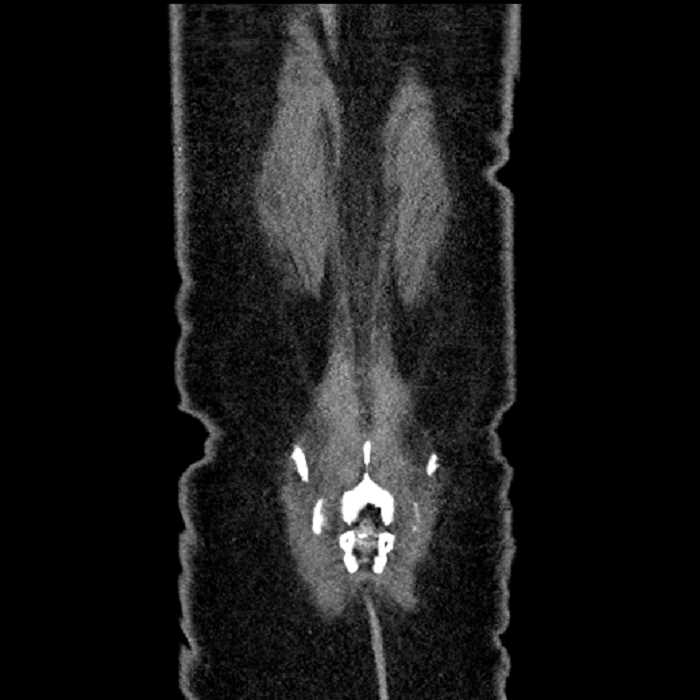

• Large fluid density structure in hepatic segments 7 and 8 measuring 10 x 7 x 7 cm with internal septation and circumferential ill-defined low density compatible with edema

• Peripherally enhancing subcapsular collections along the anterior margin of the left hepatic lobe measuring 3 x 1 cm and 2 x 1 cm

• Clearly marginated fluid density structure in segment 7 and several other scattered tiny hypodensities, which likely represent cysts

Acute sigmoid diverticulitis complicated by a small contained perforation and a large abscess in the right hepatic lobe. Additional small subcapsular abscesses along the anterior margin of the left hepatic lobe.

• The classic CT imaging appearance is a double target sign with internal low density surrounded by an internal enhancing rim (capsule) and a low density external rim (edema)

Hepatic abscess showing the double target sign with low density internally surrounded by a thin inner enhancing rim (red arrow) and ill-defined outer low density rim (yellow arrow). Blue arrow indicates an internal septation. Red arrows: additional smaller subcapsular abscesses. Red arrow: focal contained perforation associated with diverticulitis.